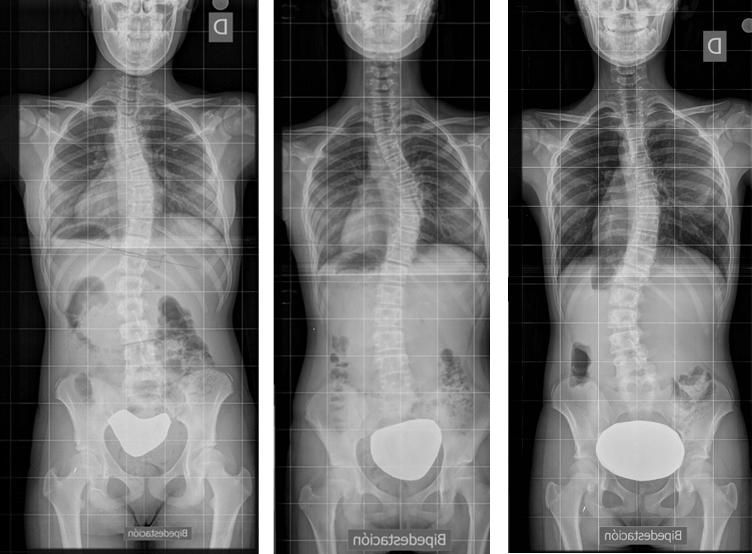

La escoliosis puede presentar una o varias curvas y en su evolución, no mejora (Figura 8). Por eso, se hace imprescindible su seguimiento con sucesivas telerradiografías, lo cual obliga, éticamente, a optimizar su estudio8.

La localización de estas curvas puede ser torácica, lumbar, o toraco-lumbar. Normalmente existe una, la llamada curva principal, sobre la que asienta la mayor deformidad rotacional. Recordemos que la escoliosis es una deformidad tridimensional en la que el raquis gira sobre sí mismo. Generalmente se acompaña de otra curva llamada secundaria a la primera en un intento de equilibrar en conjunto la columna.

Cada curva se define entre dos vertebras, al inicio y al final de esta. Son las “vértebras límite”, las cuales se identifican como aquellas a partir de las cuales la curva cambia de dirección y, por ende, tienen la mayor inclinación hacia el lado cóncavo de la escoliosis. Se eligen de tal manera que entre ellas formen el mayor ángulo posible y corresponden a aquellas con la superficie del platillo vertebral más inclinado hacia la concavidad (Figura 9).

Figura 9. Angulo de Cobb e índice de Moe de la escoliosis. El ángulo de Cobb se determina entre las dos vértebras que están más inclinadas hacia la concavidad, límites a su vez de la curva escoliótica. El índice de Moe valora la imagen asimétrica de los pedículos y da información de la importancia de la rotación de la vértebra ápex. Mostrar/ocultar

Existen distintas formas de medir el ángulo de esta curva, pero el más frecuente es el ángulo de Cobb. Este ángulo está definido entre dos líneas que pasan, una de ellas paralela por el platillo superior en la vértebra límite superior y la otra por el platillo inferior de la vértebra límite inferior.

Normalmente en el centro de la curva se localiza la vertebra ápex (aunque a veces el ápex de la curva es un disco intervertebral). Corresponde al punto con mayor desplazamiento lateral desde eje central de la columna. Es la vértebra más deformada, la que está más rotada. En esta vértebra se mide el índice de Moe que determina la situación, más o menos centrada, de los dos pedículos (Figura 9). Cuanto más en el ápex y cuanto más rotada, el índice de Moe es mayor porque la vértebra proyecta los pedículos en posición asimétrica. Las apófisis espinosas también se deforman apuntando a la concavidad.

Las costillas en la zona de la concavidad tienen mayor verticalización y el espacio intercostal está disminuido, mientras que, por el contrario, en la zona de la convexidad están más horizontalizadas y separadas, y en la zona posterior próxima a su origen en la vértebra, hacen una curva muy aguda (Figura 10).

Todo esto explica la repercusión estética (signo de Adams) y pulmonar de la escoliosis. Y esto nada más, define una escoliosis. En la Figura 11 se puede observar una grave escoliosis con una perfecta simetría en los hombros, pelvis y caderas.

Figura 11. Simetría en los hombros pelvis y caderas con una grave escoliosis dorsal. Mostrar/ocultar